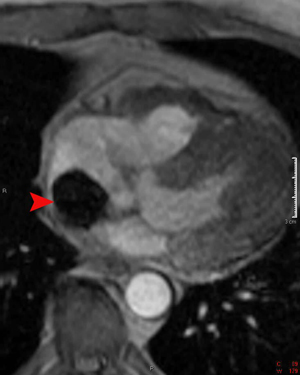

This gradient echo image demonstrates a myxoma in the right atrium (arrowhead). The myxoma has very low signal intensity due to the thrombus and chronic blood products.

Myxomas are the most common primary cardiac tumor. They tend to occur in middle aged patients and are more common in women then men. Patients may have peripheral embolization of the tumor, obstruction of an atrial-ventricular valve, or symptoms of a systemic disease (fever, malaise, etc). They are typically pedunculated masses located in the left atrium. T1-weighted spin echo images show a mass with intermediate signal intensity similar to myocardium. However, this signal may be variable due to calcifications that are hypointense or hemorrhage that is hyperintense to myocardium. On gradient echo images, myxomas usually have a signal lower than the surrounding blood. Myxomas typically enhance heterogeneously.